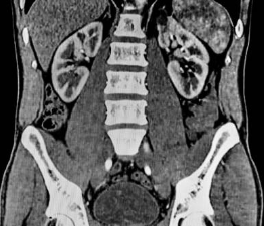

CT(Computed Tomography)는 X선을 사용하여 3차원 이미지를 생성하는 의료 영상 검사 기술 중 하나입니다. CT는 신체의 다양한 부위를 정확하게 촬영할 수 있어서 다양한 진단에 이용됩니다. 특히 뇌, 흉부, 복부 등의 내부 구조를 세밀하게 살펴볼 수 있어서 진단과 치료 계획에 큰 도움을 줍니다.

복부 CT는 복부 내부의 장기와 혈관, 림프절 등을 자세하게 촬영하여 그림으로 나타내는 영상진단 방법 중 하나입니다. 복부 CT를 통해 확인 가능한 질병은 매우 다양합니다.

- 담낭, 췌장, 간, 비장, 신장 등의 종양: 복부 CT는 위장관 종양 및 다른 내장의 종양을 확인하는 데 유용합니다. 담낭, 췌장, 간, 비장, 신장 등 다양한 내장의 종양이 존재할 수 있으며, 복부 CT를 통해 종양의 위치와 크기를 파악할 수 있습니다.

- 담낭염: 복부 CT는 담낭의 염증을 확인하는 데 유용합니다. 담낭염은 담석, 감염, 알코올 소비 등이 원인이 될 수 있으며, 복부 CT를 통해 담낭염의 정도를 확인할 수 있습니다.

- 신장 결석: 복부 CT는 신장 내에 결석이 있는지 확인하는 데 유용합니다. 신장 결석은 신장 내에서 석회나 요산염이 축적되어 결석이 형성되는 질병으로, 복부 CT를 통해 결석의 크기와 위치를 파악할 수 있습니다.

- 대장암: 복부 CT는 대장암 진단에 중요한 역할을 합니다. 대장암은 장의 상피세포에서 암세포가 발생하는 질환으로, 복부 CT를 통해 대장암의 위치와 정도를 파악하여 치료 방법을 결정할 수 있습니다.

- 충수염: 복부 CT는 충수의 염증을 확인하는 데 유용합니다. 충수는 대장의 일부이며, 충수염은 충수의 염증으로 복부 CT를 통해 염증의 정도와 위치를 파악할 수 있습니다.

복부 CT는 진단에 대한 정확성이 높고 비침습적인 방법으로 장기나 혈관의 구조나 기능상의 이상을 파악할 수 있어, 내과, 외과, 신경과, 영상의학과, 방사선종양학과 등 다양한 분야에서 활용되고 있습니다.